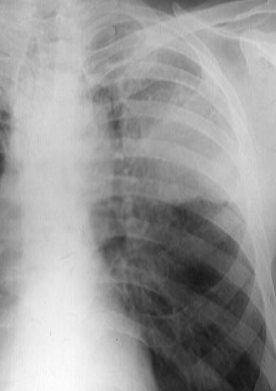

Rx toracică, incidență P-A

DESCRIERE:

la niv. întregului hemitorace drept → opacitate extinsă, nesistematizată, de intensitate mare, omogenă

caracter expansiv → împinge traheea și mediastinul de partea opusă

diafragm deplasat în jos

lărgirea spațiilor intercostale

umplerea spațiului costo-diafragmatic

DX: pleurezie masivă

DD: atelectazie → caracter retractil